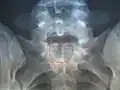

- Spina bifida occulta

- Occulta bedeutet „verborgen, nicht sichtbar“. Diese Form der Spina bifida ist dadurch gekennzeichnet, dass sich nur ein zweigespaltener Wirbelbogen findet, ohne dass das Rückenmark mit seinen Rückenmarkshäuten (Meningen) beteiligt ist. Sie ist darum nicht von außen sichtbar. Die Spina bifida occulta ist recht häufig und wird oft nur zufällig bei Röntgenaufnahmen oder einer Untersuchung des Rückens festgestellt. Besonders bei bettnässenden Kindern wird die Spina bifida occulta auffallend häufig gefunden. In der Regel hat sie medizinisch keine besondere Bedeutung; eine Behandlung ist nicht nötig. Ein Dermalsinus kann vorkommen.

Spina bifida occulta am 5. Lendenwirbel

Spina bifida occulta am Kreuzbein

Spina bifida occulta am Kreuzbein

Die Spina bifida occulta wird in der Regel nur zufällig festgestellt.